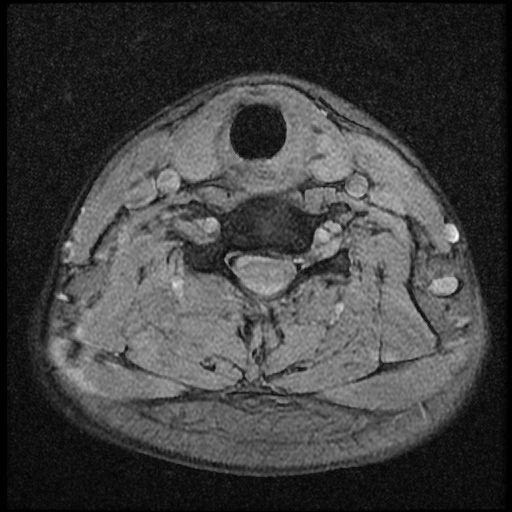

이 MRI 사진은 21년도 사고 당시 찍은 MRI 사진 입니다. 확인 부탁드립니다~

전체 mri를 다 봐여겠지만 보여주신 mri 컷에서는 의미있는 경추 디스크탈출이 보이지 않습니다.